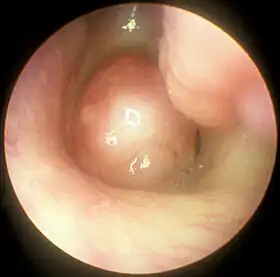

Large nasal polyp (round mass, center), which is commonly treated and removed by FESS

Functional endoscopic sinus surgery is most commonly used to treat chronic rhinosinusitis (CRS),[8] only after all non-surgical treatment options such as antibiotics, topical nasal corticosteroids, and nasal lavage with saline solutions[9] have been exhausted. CRS is an inflammatory condition in which the nose and at least one sinus become swollen and interfere with mucus drainage.[9] It can be caused by anatomical factors such as a deviated septum or nasal polyps (growths), as well as infection. Symptoms include difficulty breathing through the nose, swelling and pain around the nose and eyes, postnasal drainage down the throat, and difficulty sleeping.[10] CRS is a common condition in children and young adults.[11]

The purpose of FESS in treatment of CRS is to remove any anatomical obstructions that prevent proper mucosal drainage. A standard FESS includes removal of the uncinate process, and opening of the ethmoid air cells and Haller cells[12] as well as the maxillary ostium, if necessary. If any nasal polyps obstructing ventilation or drainage are present, they are also removed.[8] In the case of paranasal sinus/nasal cavity tumors (benign or cancerous), an otolaryngologist can perform FESS to remove the growths, sometimes with the help of a neurosurgeon, depending on the extent of the tumor. In some cases, a graft of bone or skin is placed by FESS to repair damages by the tumor.[13]